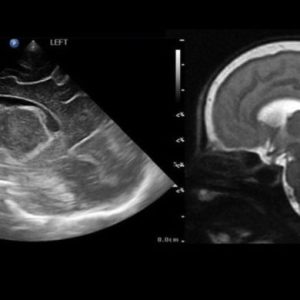

Allo stato attuale, in molte realtà vengono utilizzati gli ultrasuoni per analizzare la struttura cerebrale dei piccoli.

Secondo il parere del prof. Paul Griffiths, della University of Sheffield, la RM sarebbe molto più efficace per rilevare anomalie morfologiche cerebrali.

È tuttavia possibile visionare il cervello dei neonati prematuri con gli ultrasuoni, poiché le suture del cranio non sono ancora fuse tra loro.